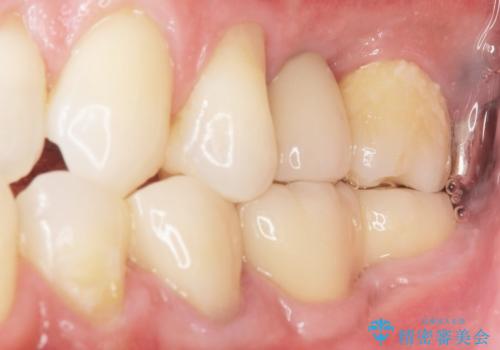

「違和感もなく、まるで自分の歯のようにしっかり咬めます!」と大変喜んで頂けました。

インプラントの種類:ストローマン BLT

被せ物の種類:オールセラミッククラウン スタンダード